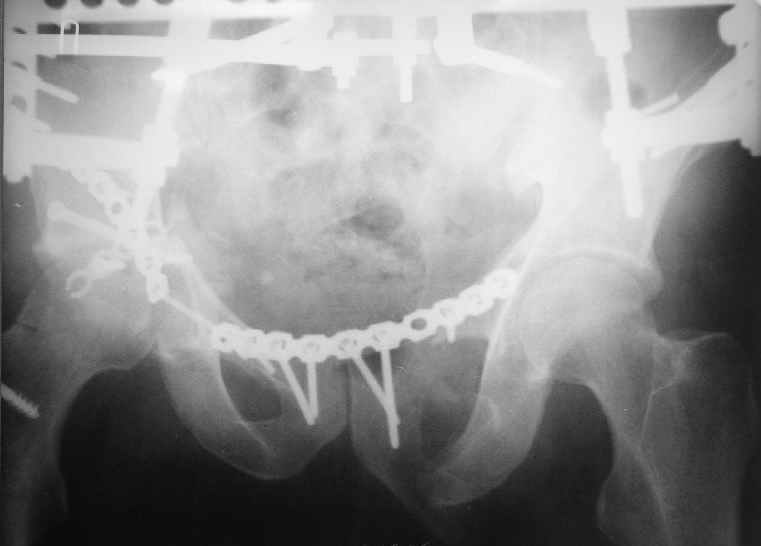

Доступ чрезвертельный, лучше Y образный, хотя при хорошем опыте можно и задне наружным (вертел придется отсекать).

Фиксация передней колонны трансфрактурным винтом, задней пластинами,мостовидной и упорной.

Разрыв лонного сочленения можно зафиксировать сразу после фиксации вертлуги из второго доступа.

Высылаю нечто подобное, аппарат пусть не смущает, просто больного оперировал через 2 месяца после травмы, а у него еще полный разрыв кп сочленения с контрлатеральной стороны.